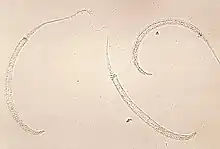

Dracunculus medinensis larvae

Dracunculiasis is also known as Guinea-worm disease. In 2019, 53 cases were reported across four countries,[44] a substantial decrease from 3,500,000 cases in 1986.[45] It is not fatal, but can cause months of inactivity.[46] It is caused by drinking water contaminated by water fleas infected with guinea-worm larvae.[46] Approximately one year after infection, a painful blister forms and one or more worms emerge. Worms can be up to 1 metre long.[46]